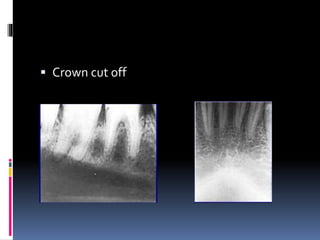

 Crown cut off

 Region of interest not shown